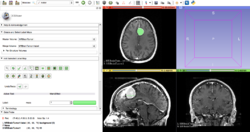

- Slicer 4.0 includes a major overhaul of the user interface, improved and simplified workflows for major tasks, simplified procedures for developers, and improved Python support.

Slicer is a community platform created for the purpose of subject specific image analysis and visualization.

- Multi-modality imaging including, MRI, CT, US, nuclear medicine, and microscopy

Slicer Highlights